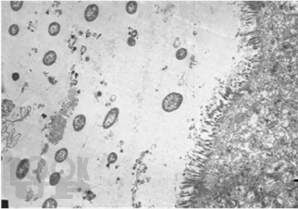

В книге приводятся сведения о микробиоте репродуктивного тракта женщин в норме и при гестации с учетом влияния на нее нормальной микрофлоры кишечника. Впервые представлена динамика заселения нормальной микрофлорой организма новорожденных при естественном и абдоминальном способах родоразрешения. Показано, что в формировании микробиоты новорожденного доминирующую роль играет микрофлора кишечника матери, при этом колонизация возможна как при естественном контакте, так и при транслокации бактерий из  различных биотопов матери в системный кровоток плода. Материалы по микробному пейзажу вагинального биотопа женщин и предоставленная в книге клинико-лабораторная характеристика бактериальных вагинозов, так же, как и оценка микробного пейзажа новорожденных имеют важное значение для прогнозирования бактериального инфекционного процесса.